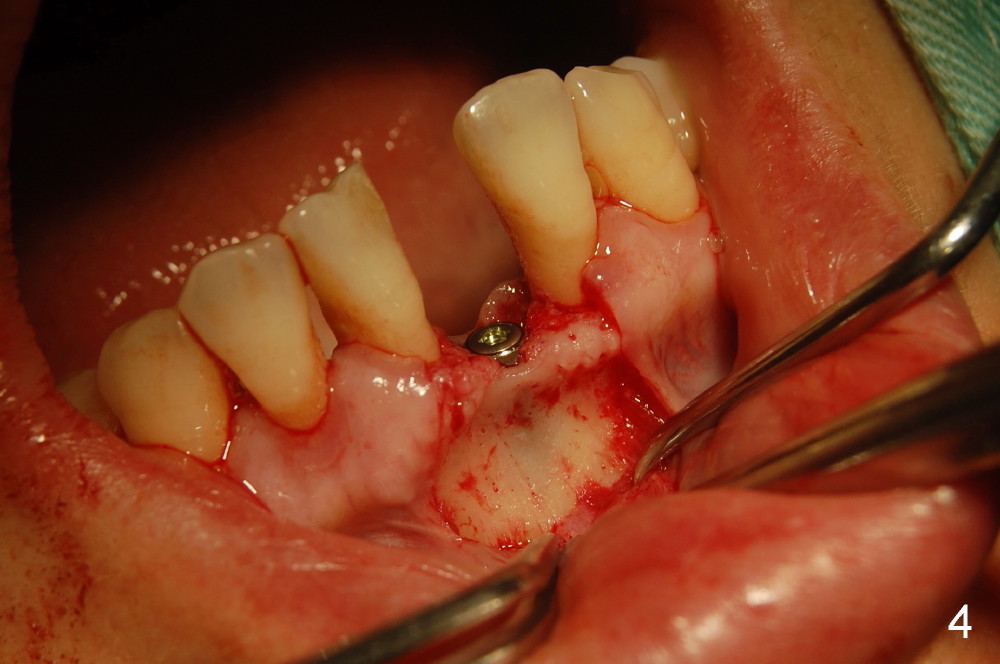

2,左下1舌侧附着龈切口,翻开唇侧粘骨膜瓣,测量牙槽嵴唇舌侧厚度仅4mm,唇侧牙槽嵴下方明显凹陷,约厚3.5mm。证实了术前预估的骨量情况,如孔道唇侧侧壁穿孔就植骨粉,已和病人交待。

为了提高种植体的稳定性,钻孔时小心翼翼,长轴的近远中特别是唇舌侧角度一点都不敢大意,只打了两钻,非常幸运没有侧穿!!但孔道侧壁骨壁可透光,住院医的手术记录为”薄如蝉翼“,”妙“。(终于没白教她们,懂得了体会其难度)

不敢打第三钻了,改为攻丝,植入3.3x12mm骨水平美学种植体,透过骨壁种植体清晰可见。

所以,还是在唇侧骨面上种植体的两旁各打了几个小眼使其出血,植入Bioss骨粉,上覆盖Biosmate骨膜,减张包埋缝合。

附上照片一阅。